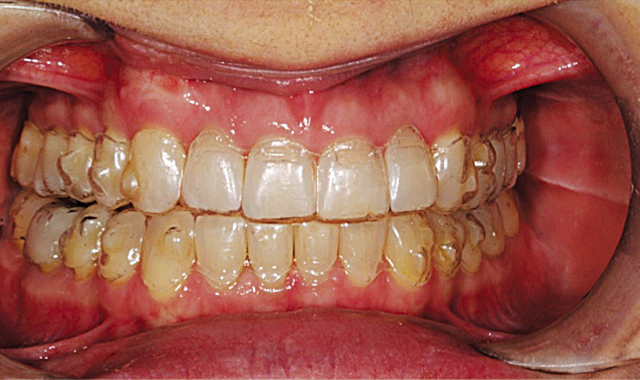

This patient presented with concerns over the esthetics of her smile due to the shifting of her teeth over time (Figs. 1-3). We diagnosed crowding and asymmetry of her teeth and gingival tissues. Our treatment plan included Invisalign treatment, occlusal equilibration after orthodontics and Vivera retainers.

Our Invisalign treatment led to a very successful clinical result. The crowding and the asymmetries of tooth position, arch form and gingival levels were beautifully corrected (Figs. 14-16).